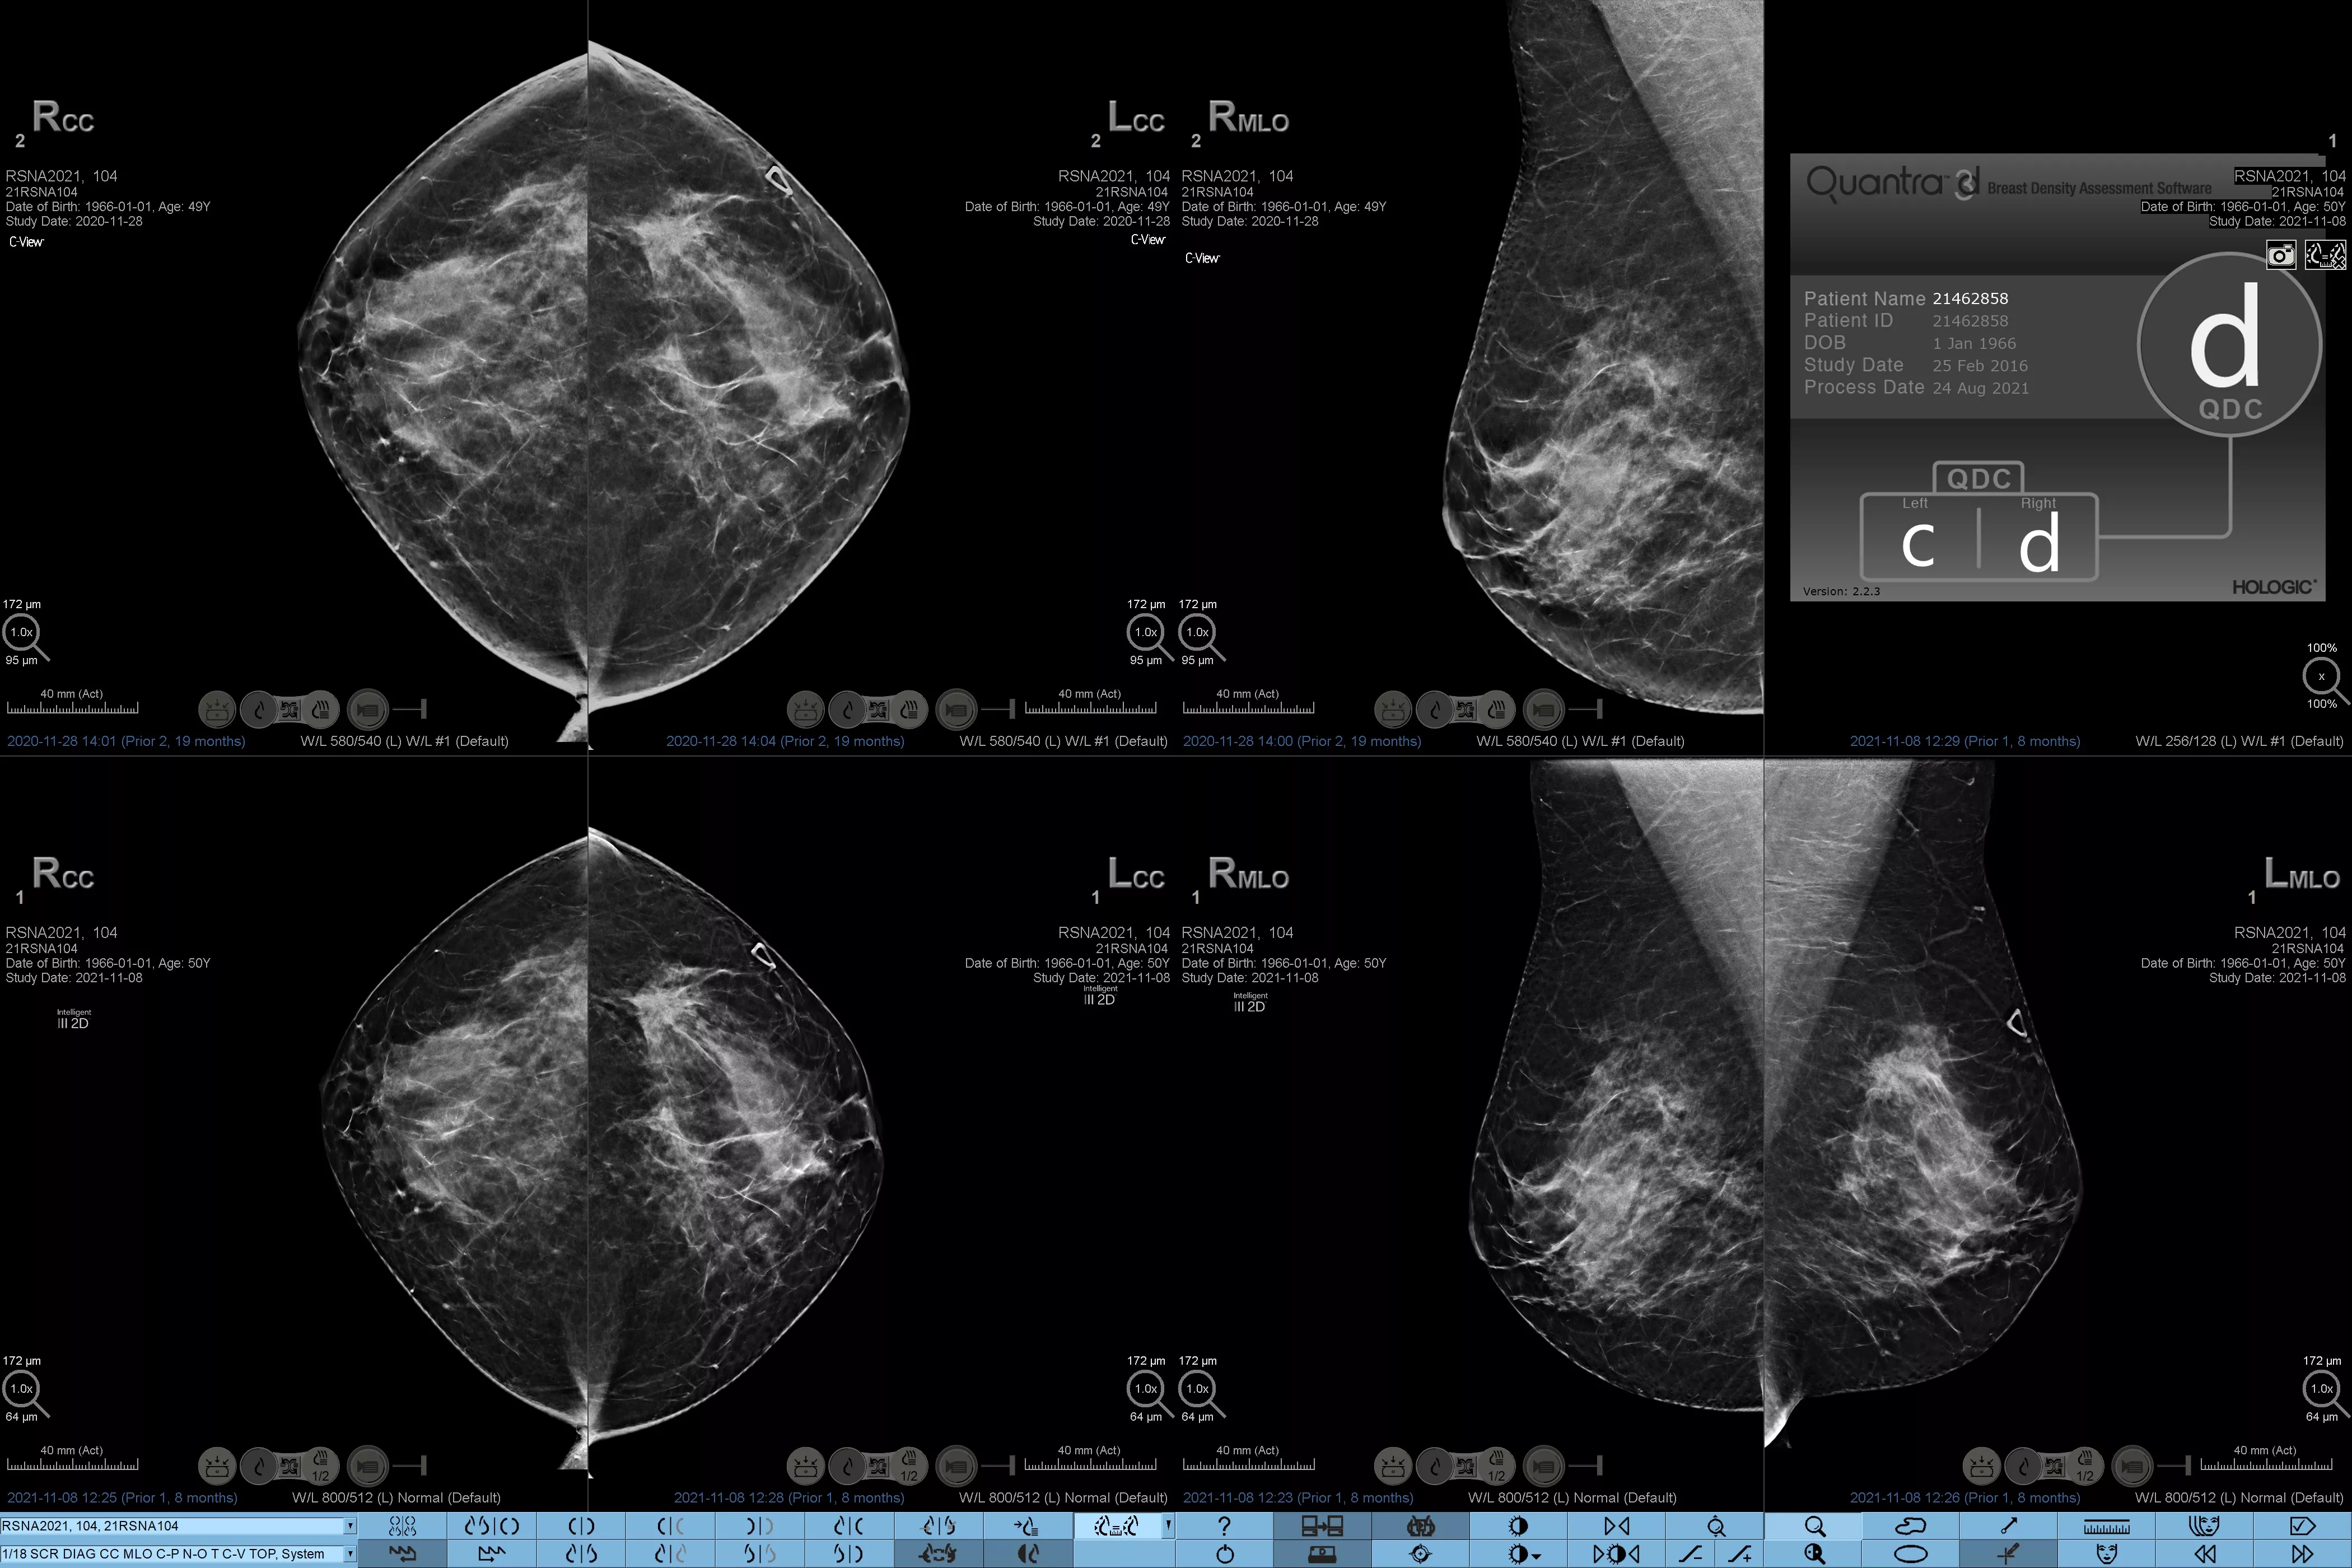

Higher breast density is known to increase a woman’s risk for breast cancer.1 The need for accurate, unbiased analysis is therefore critical. Powered by machine learning, Quantra technology software analyses both 2D™ and tomosynthesis images for distribution and texture of parenchymal tissue. It categorises breasts in four breast composition categories consistent with guidance from the American College of Radiology (ACR) BI-RADS Atlas 5th Edition.2

Breast imaging scans

8. Breast composition categories as described in ACR BI-RADS Atlas.